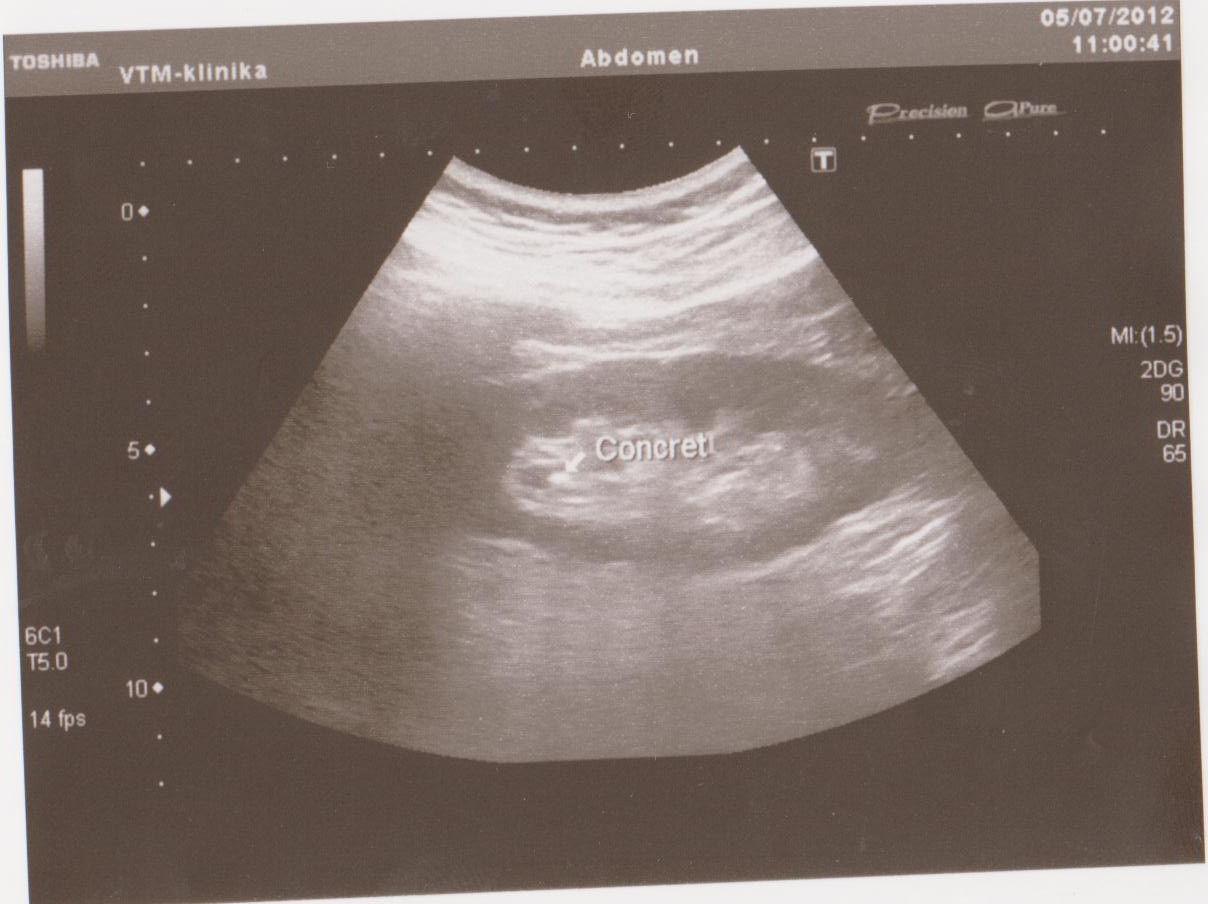

Ниже я привел пару УЗИ снимков из практики, все они есть в галерее УЗИ на сайте, смотрите и не пугайтесь: